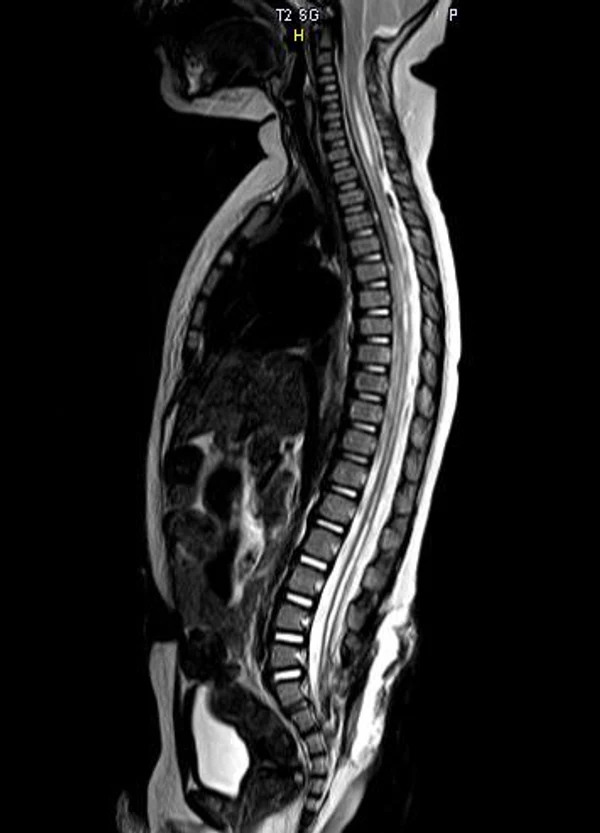

В своей практике с сирингомиелией мы сталкиваемся, как правило, в виде сочетанной аномалии у пациентов со спинальными дизрафизмами и/или аномалией Арнольда-Киари. Операции проводятся при увеличении размеров сирингомиелической полости в динамике, появлении или нарастании патологической неврологической симптоматики. При локализации сирингомиелии на шейном уровне, как правило, причиной ее развития является аномалия Арнольда-Киари. Хирургическое лечение заключается в проведении субокципитальной краниоэктомии, С1-2 ламинэктомии, устранение спаек в области большой цистерны, ревизии отверстия Мажанди и экспансивной дурапластики. После данной операции сирингомиелическая полость, как правило, регрессирует или уменьшается в размерах. Причиной сирингомиелии также может служить укороченная и утолщенная терминальная нить. В таких случаях первично выполняется рассечение терминальной нити. В остальных ситуациях при прогрессировании сирингомиелии на грудном или поясничном уровнях нами выполняется устранение фиксации спинного мозга на уровне сирингомиелии и сиринго-субарахноидальное шунтирование с помощью тонкого силиконового катетера (рис. 15).